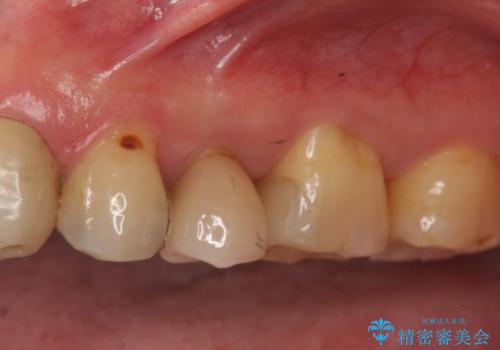

歯の表面の黒いところは虫歯ではなく

歯ブラシによる摩耗か歯ぎしりによるくさび状欠損によるものです。

そのままだと水などが染みてくる原因にもなります。